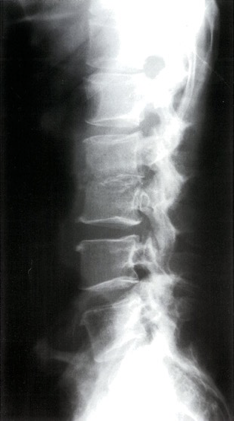

Spinal

PLAIN FILMS

- Narrowing and destruction of an intervertebral disk

- Paravertebral soft tissue mass

- Endplate sclerosis (during healing phase)

Spondylodiscitis (discitis-osteomyelitis)

X-ray lumbar spine (lateral view)

The inferior endplate of L2 and superior endplate of L3 are osteopenic and the cortices appear fragmented. The intervening L2–3 disc space is narrowed.